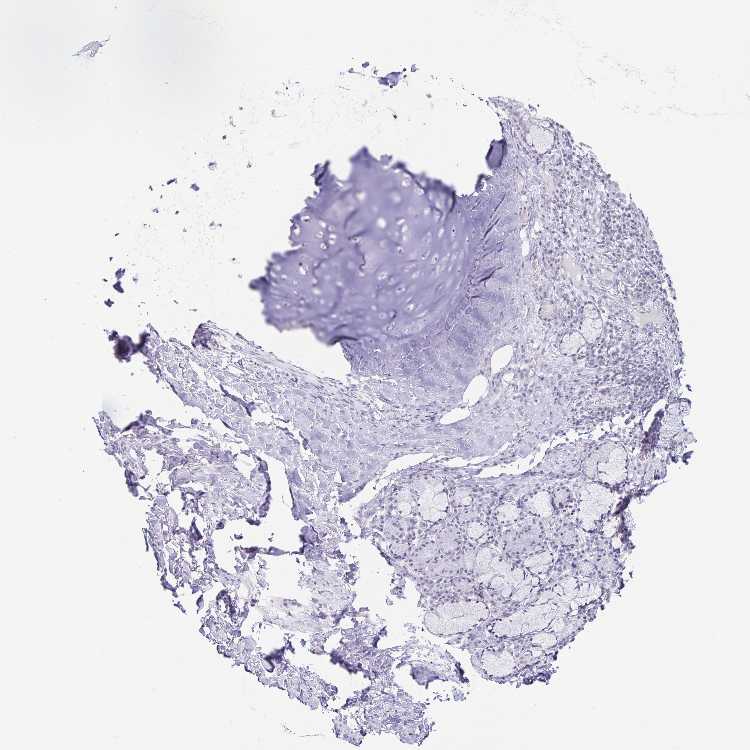

SOFT TISSUE 1 - Antibody stainingi

Antibody staining in the annotated cell types in the current human tissue is reported as not detected, low, medium, or high, based on conventional immunohistochemistry profiling in selected tissues. This score is based on the combination of the staining intensity and fraction of stained cells.

Each image is clickable and will lead to virtual microscopy that enables deeper exploration of all samples and also displays staining intensity scores, fraction scores and subcellular localization as well as patient and tissue information for each sample.

Antibody HPA046376

Chondrocytes Not detected

Fibroblasts Not detected